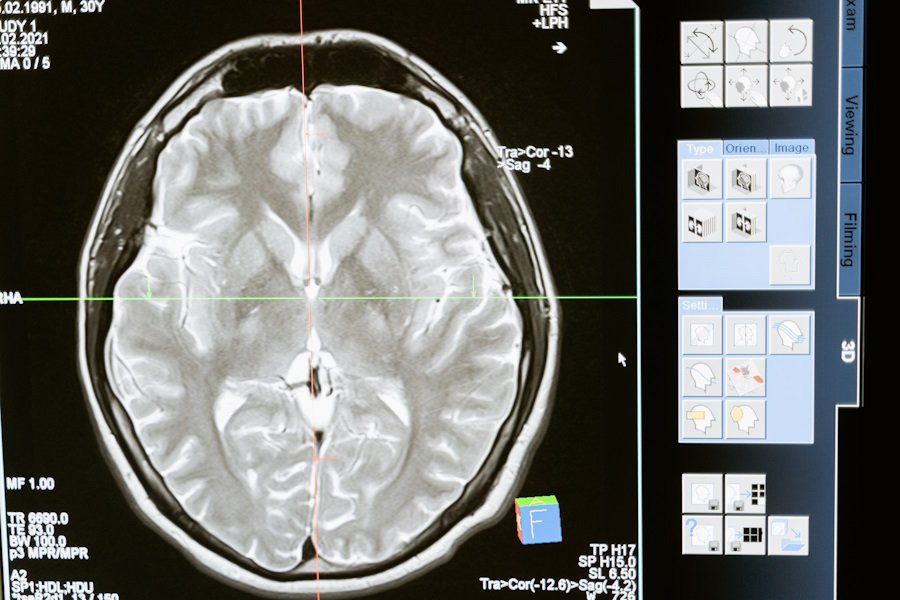

В мозге выявлен «клей», служащий консолидации памяти

Исследователи из State University of New York сделали важное открытие, связанное с функцией молекулы KIBRA в деле консолидации памяти. Результаты их работы были опубликованы на портале Science Advances.

Ранее считалось, что память формируется исключительно за счет прочности связей между нейронами. Однако новое исследование показало, что белок KIBRA играет роль своеобразного «клея», который помогает поддерживать эти связи. Это открытие опрокидывает старую теорию и показывает, что KIBRA необходим для долгосрочного сохранения воспоминаний.

Ученые объясняют, что белок KIBRA взаимодействует с другими молекулами в мозге, чтобы предотвратить потерю воспоминаний. Несмотря на то, что KIBRA существует всего несколько дней, за это короткое время он успевает сыграть ключевую роль в поддержании нейронных связей.

Эксперименты на грызунах подтвердили, что KIBRA действительно важен для сохранения памяти. Этот белок не только участвует в формировании новых воспоминаний, но и является критическим элементом в механизме запоминания.

Понимание основных клеточных функций KIBRA может стать важным шагом на пути к лечению и профилактике нейродегенеративных заболеваний.